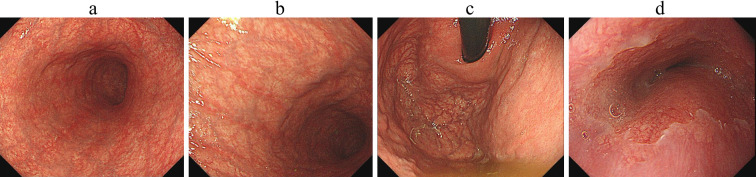

2020年,一名56岁女性,9年前有幽门螺杆菌根除史,出现出血性增生性息肉。内镜和组织学检查结果导致晚期自身免疫性胃炎(AIG)的诊断。回顾2014年的内镜检查结果,窄带成像显示胃区肿胀,早期AIG的特征。再加上增生性息肉的快速生长,这些发现提示AIG在根除后迅速恶化。据我们所知,这是第一例在根除幽门螺杆菌后迅速发展的出血性增生性息肉与AIG相关的病例报告。

In 2020, a 56-year-old woman with a history of Helicobacter pylori (H. pylori) eradication 9 years previously presented with a hemorrhagic hyperplastic polyp. Endoscopic and histological findings led to the diagnosis of advanced-stage autoimmune gastritis (AIG). A review of endoscopic findings from 2014 was available, and narrow-band imaging showed swelling of the gastric areas, characteristic of early-stage AIG. Together with the rapid growth of a hyperplastic polyp, these findings suggest a case of AIG that rapidly exacerbated after eradication. To our knowledge, this is the first case report of a rapidly developing hemorrhagic hyperplastic polyp associated with AIG after H. pylori eradication.